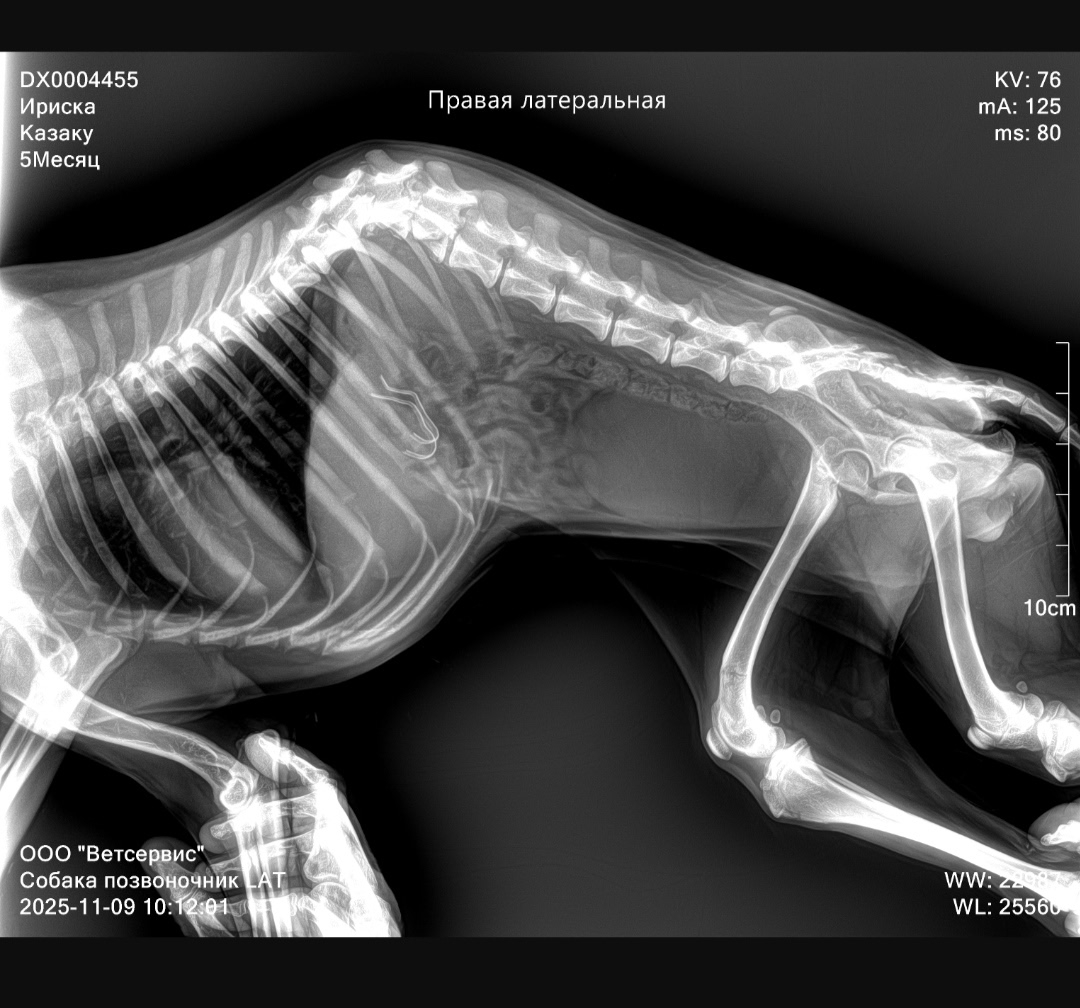

В ходе ветеринарного осмотра выяснилось, что в желудке у собаки находятся металлические скобы. Кроме того, щенок получил перелом шейки бедра и позвоночника. Как заключили специалисты, спинной мозг погиб в месте перелома, из-за чего неврологическое восстановление животного оказалось под угрозой. Мнения питерских и кировских ветеринаров по вопросу спасения разошлись: помимо восстановления возник вариант усыпить собаку.